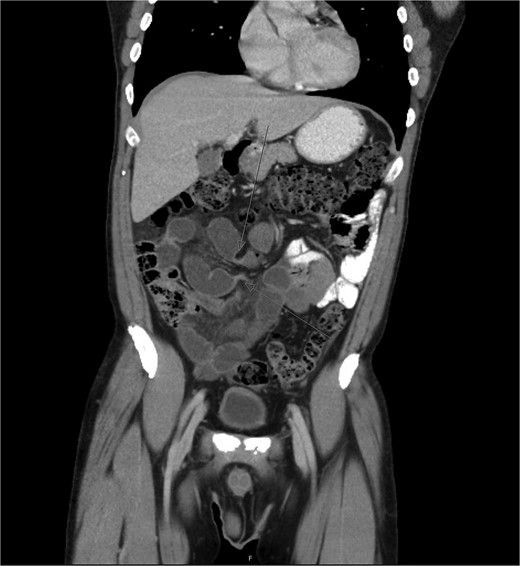

A CT abdomen and pelvis with oral and intravenous contrast revealed a closed-loop small bowel obstruction, with dilated loops of small bowel in the right mid to lower abdomen and associated mesenteric fluid (Fig. 1). A nasogastric tube was inserted, and the patient was taken for emergency surgery.

Abdominal CT scan demonstrating closed-loop small bowel obstruction involving jejunal loops, with two distinct transition points indicated by arrows.